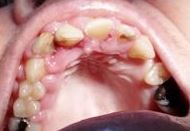

Volver a los detalles del artículo Hiperplasia gingival inducida por amlodipino en paciente con periodontitis crónica. Presentación de un caso